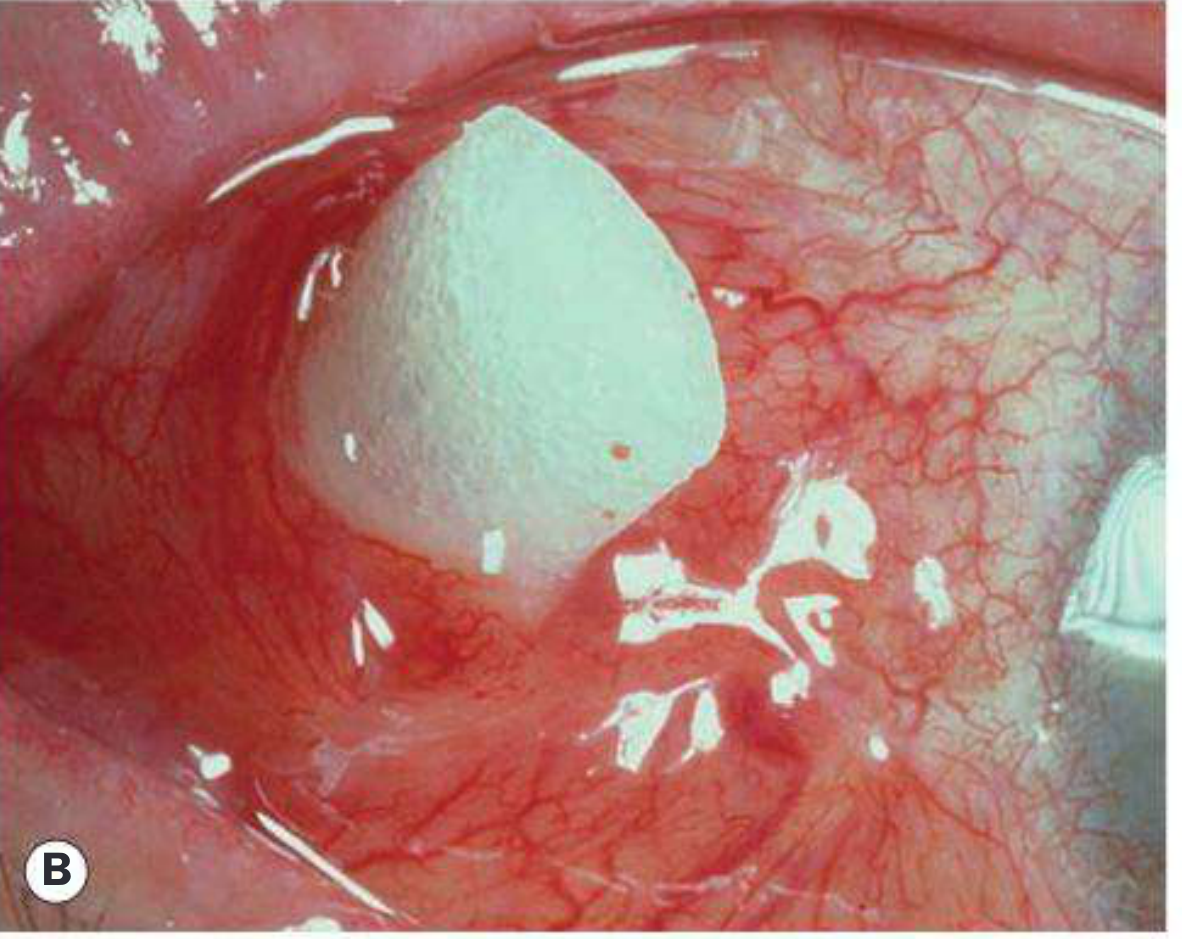

Scleral buckling — wide-field view showing buckle induced by radial explant (A) and circumferential explant (B)

Fig. 16.29 — Wide-field fundus view showing the buckle effect (A) radial explant; (B) circumferential explant